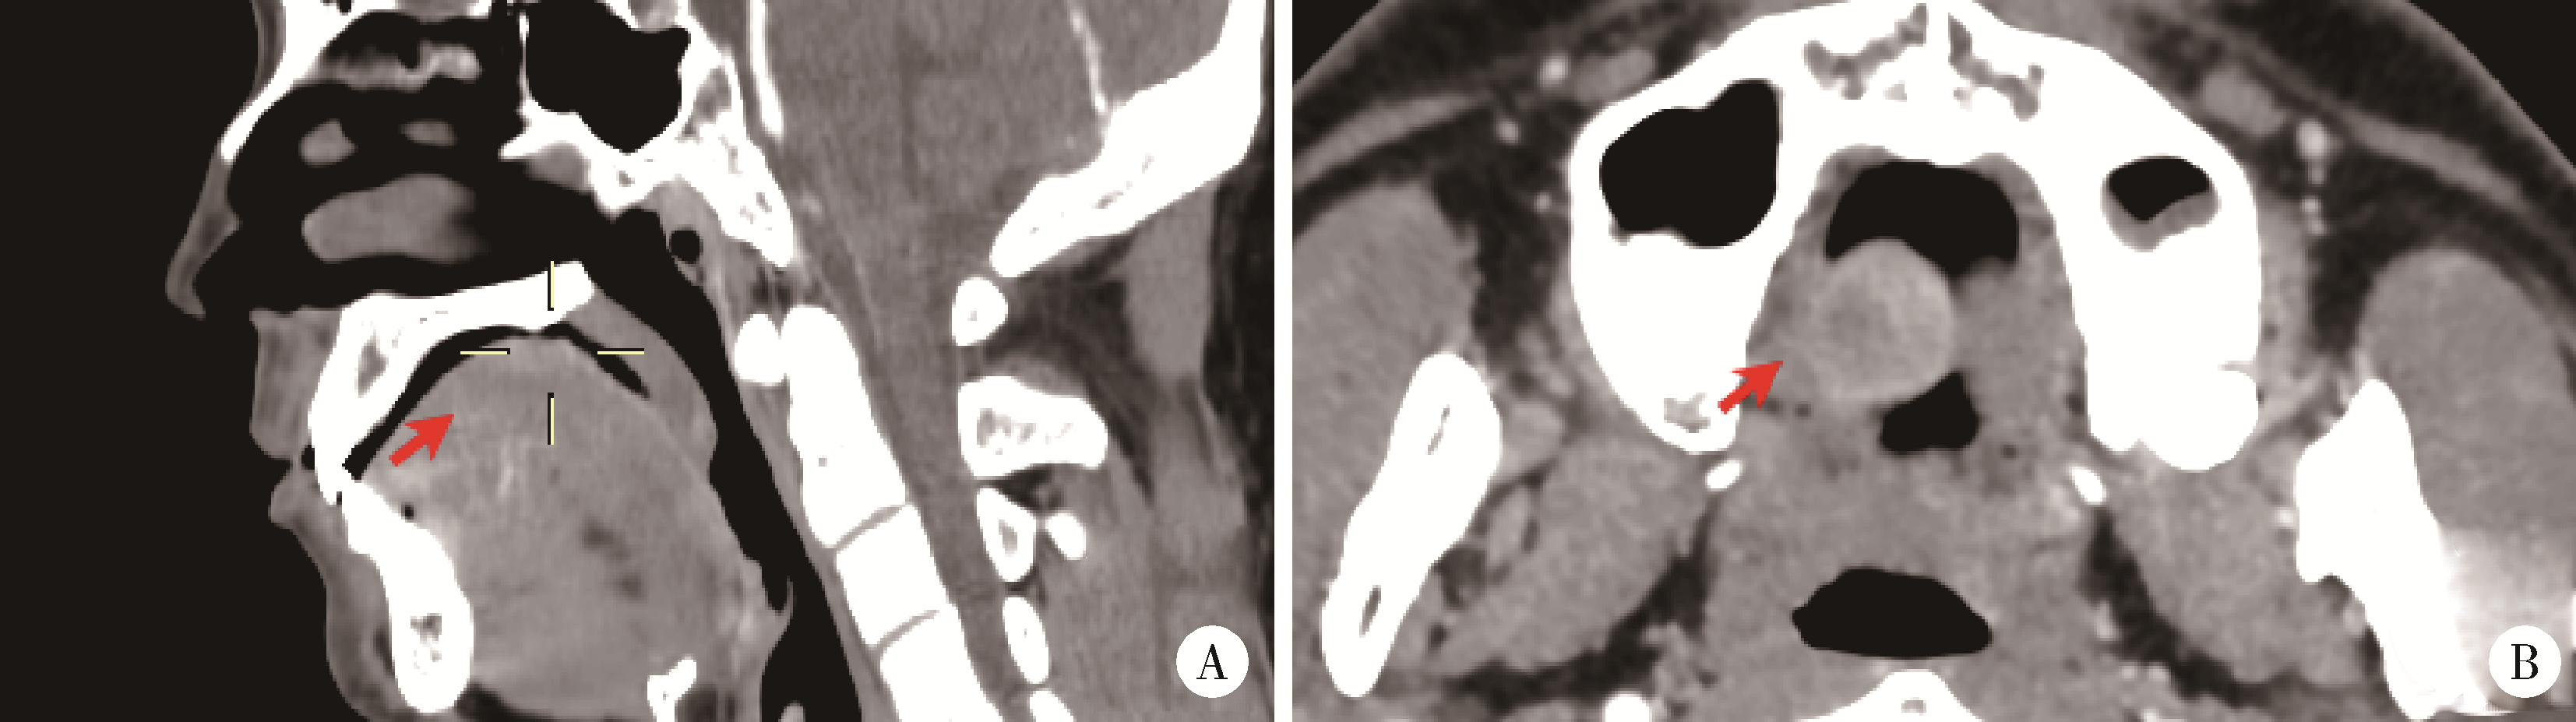

病例1为男性,30岁,主因“发现舌背肿物1周”就诊。患者就诊一周前疑似进食不洁食物后舌背出现肿物,初为黄豆大小,自觉异物感,后肿物迅速增大,表面出现白色假膜,可自行揭开,少量出血后可自止,伴轻度疼痛,未行诊治。自述既往进食不洁食物后四肢曾出现红疹;既往淋病史。否认食物和药物过敏史。专科检查:舌背正中偏右可见一直径2 cm类圆形溃疡,隆起于黏膜,溃疡表面有白色假膜覆盖,不均匀,溃疡周围黏膜充血水肿。扪诊溃疡基底有硬结,轻度触痛(图 1)。头颈部CT示舌背正中类圆形软组织肿物影,边界较清楚,轻度强化(图 2)。实验室检查:白细胞计数10.21×109/L(正常值为3.5×109/L~9.5×109/L);中性粒细胞比例50.6%(正常值40%~75%);中性粒细胞绝对值5.17×109/L(正常值1.8×109/L~6.3×109/L);嗜酸粒细胞比例16.3%(正常值0.4%~8.0%);嗜酸粒细胞绝对值1.66×109/L(正常值0.02×109/L~0.52×109/L)。血清IgE为5.1 IU/mL(正常 < 100 IU/mL)。唾液涂片镜检可见革兰阳性球菌、革兰阴性杆菌,未见念珠菌菌丝。临床初步诊断为舌背肿物。

图2 病例1,CT显示舌背轻度强化圆形软组织肿物影(箭头示)

Figure 2 Case 1, CT showed a mildly enhanced round soft tissue mass on the dorsum of the tongue(arrowhead)